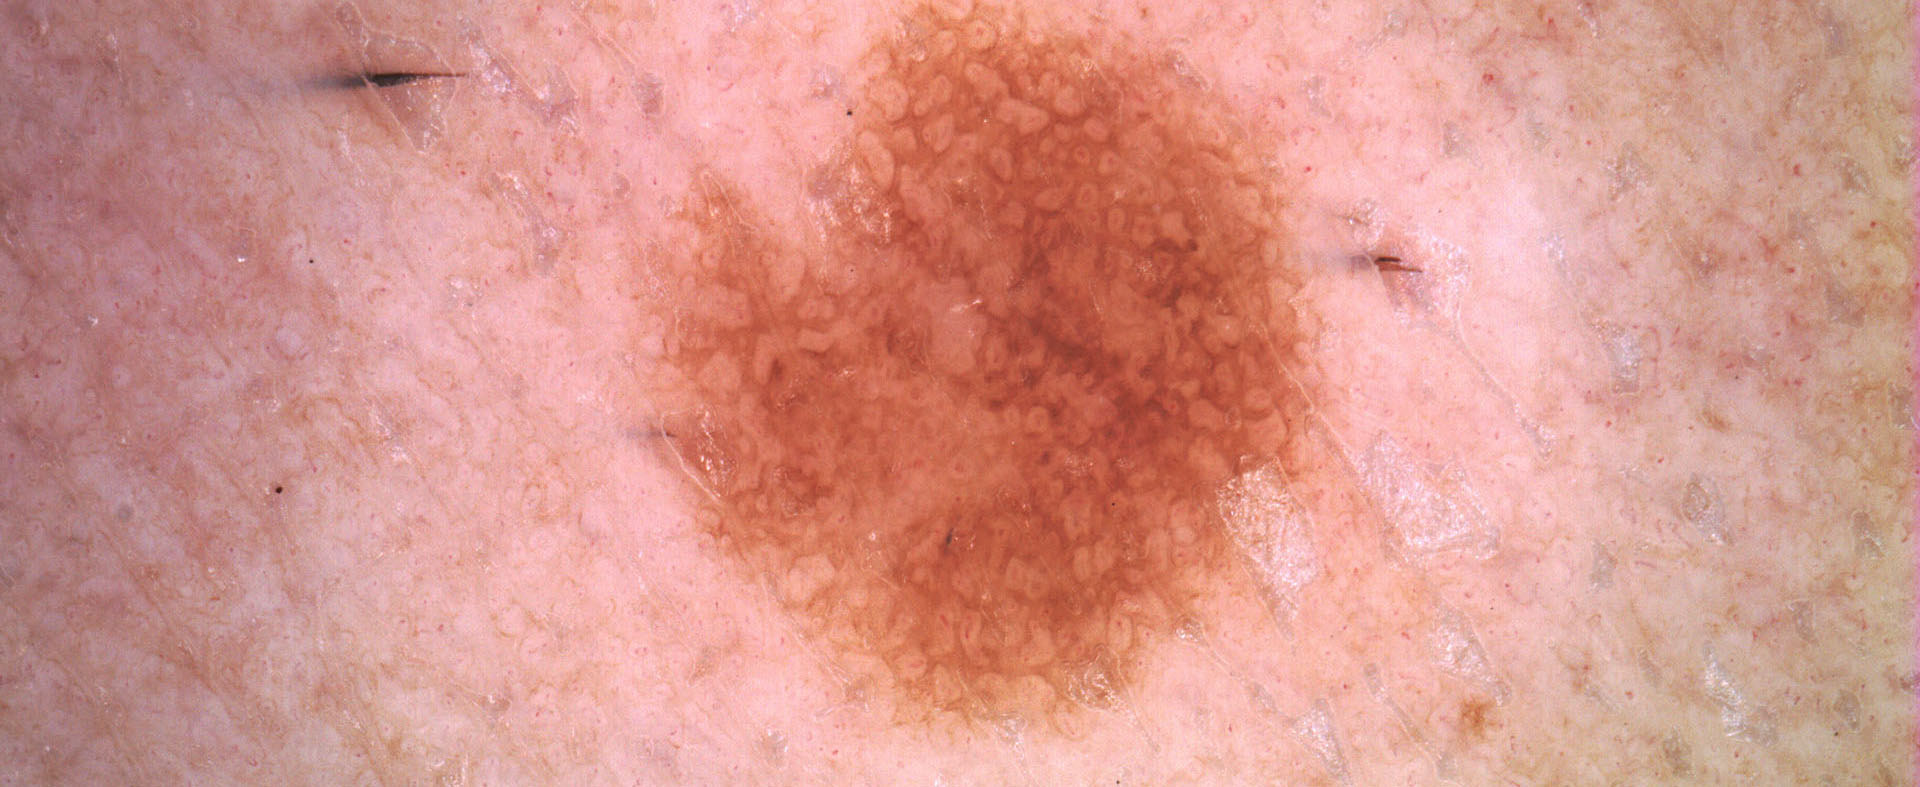

Color balance

A volte osservare le immagini dermoscopiche con una luce differente aiuta a scoprire piccoli dettagli che possono essere vitali nei processi diagnostici.

La funzione di Color Balance del software di IRSKIN professional è uno strumento algoritmico standard che bilancia le intensità di colore delle immagini acquisite.

Poiché modifica le immagini, può essere utilizzato solo nella fase di visualizzazione, semplicemente spuntando la casella Color Balance.

Dopo aver usato

color balance

Prima di usare

color balance

Dopo aver usato

color balance